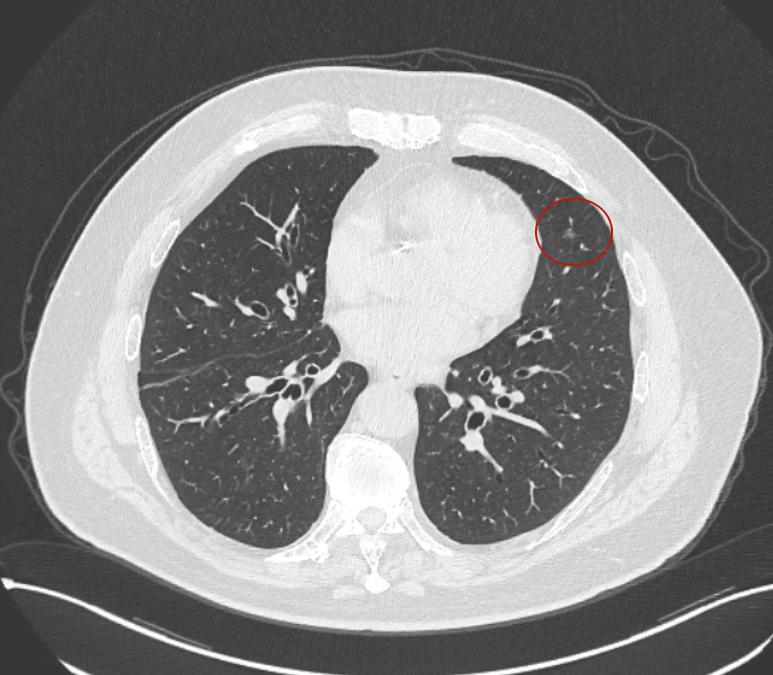

但病灶B却显然进展!变成以实性成分为主的了!

两处均有进展,混合密度这处更显著些。那要考虑手术了的。之前也有碰到较短时间内进展是伴炎症或纤维增生的,但我们不能赌。建议手术为宜。意见供参考!

再看病灶B的2026年3月细节影像特征:

边缘位置也是较淡的磨玻璃成分。

上图是混合密度,轮廓较清,瘤肺边界欠清晰。

病灶A以及他处磨玻璃结节其实进展都是不明显的,略与2022年比,病灶A稍显明显点。病灶B开始时极淡,之前进展虽有但也甚微,直到2025年9月仍是磨玻璃成分为主,只是点状少许密度稍高成分。但在最近半年内却显然进展!若从影像上判断,基本上就得是浸润性腺癌了。那有几点:一是必不能再随访;二是大小来看仍是1A期;三是从快速进展来说,可能含有部分高危亚型,比如微乳头或实体型等;四是他处的磨玻璃结节以及病灶A显然不能用病灶B的转移来解释,仍考虑是多原发早期肺癌。

结友问能否先穿刺?我是这么考虑的:你这个病灶B一是位置深,且靠近附近的血管,不容易穿刺;二是从影像变化来看,基本上肯定是恶性的,不是100%,也是95%以上的概率。刚才我又在重建看冠状位与矢状位以及各次影像,目前混合密度的其实是后来者居上,原来刚开始是它比旁边的病灶密度淡的,但它的密度不是太纯,前次你自己也说似乎有点状偏实性成分。只是最近这半年进展特别快。这说明它的恶性程度较它边上原来就比较明显的那处恶性程度高,亚型中大概率有低分化的成分。所以从目前的影像来看,要尽快手术,而且切肺叶更为稳妥些。

这是较为少见的一个病例,磨玻璃为主,而且一直瘤肺边界欠清晰的病灶何以会在之前三年均极缓慢微小变化的情况下,近半年却快速进展呢?从影像细节上看,我们能否进一步分析哪种纯磨玻璃结节可能会较快进展?结合本例,我个人的考虑是:1、病灶整体显得是磨玻璃密度,但灶内并不均匀,就如磨玻璃密度中混入细沙状;2、整体轮廓虽然较清但瘤肺边界相对来说却并不太清晰;3、邻近有血管紧挨,而且与病灶这间缺乏间隙;4、病灶密度不高,没有明显实性成分,却有灶内有细支气管通气征,说明肿瘤成分具有收缩力,却与纯磨的收缩不匹配(纯磨一般不太会有明显收缩力)。如果有上面这些特征可能要提高警惕,一是适当较短的随访间隔,二是影像细节变化要更加注意,开始变化意味着已经进入发展期,而非蛰伏期。当然是否在2025年9月时定得手术了?如果是孤立性的病灶B,且位置位于能简单楔形切除的位置,那是可以考虑的。但位置深、两肺多发,切除范围不小,再今年据肺癌诊疗指南中说的混合磨玻璃结节实性成分不足25%是非侵袭性病变,且几乎不会转移,那么按原则仍再随访显然是可以的。本例的随访变化再次表明磨玻璃密度肺癌的诊疗个体化之路仍是很漫长的,按指南原则的随访或诊疗显然不足以覆盖所有病例,总结与经验积累永远在路上。